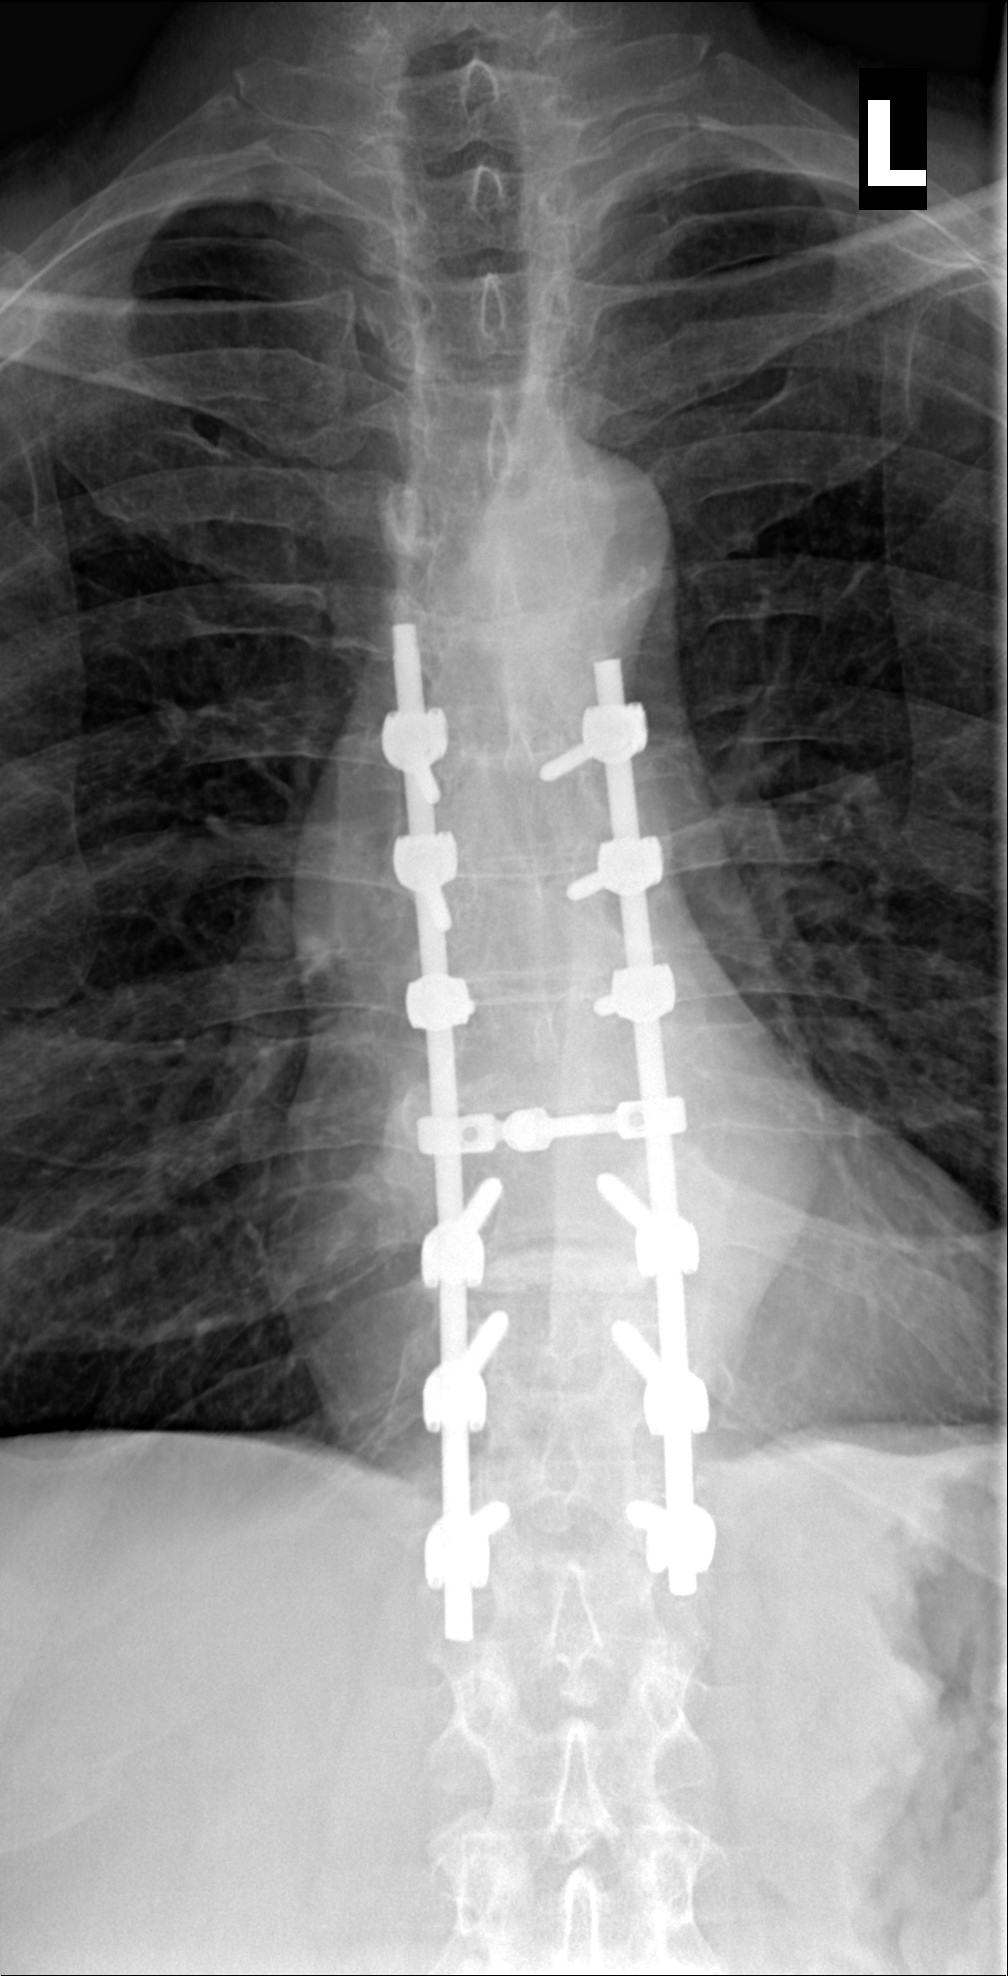

Hold my beer. I had severe back pain for 2 years and my asshat doctor and asshat local emergency room doctors put me on muscle relaxers and pain killers....for 2 years. Got worse and worse and then a gastroenterologist that I went to ordered a cat scan with contrast and found a tumor on my spinal cord that was cancerous. She called me that evening and told me to get to the emergency room immediately and they operated to remove the tumor and stabilized my spine with screws and rods. I've been going for chemo treatments for multiple myeloma for the past 12 years on and off, as I go in and out of remission. I've been in remission now for the past year and a half. Hopefully I stay in remission. I am on a new drug called Darzalex which is NOT chemotherapy. It is a targeted monoclonal antibody that helps slow or stop the progression of multiple myeloma.

xray1.jpg

xray2[5913].jpeg

That's a lot of hardware!

Not large, but it was wrapped completely around my spine and was putting pressure on my spinal cord. The back surgeon said I was millimeters away from being paralyzed from the waist down if it was not removed. I was very lucky that they found it in time.